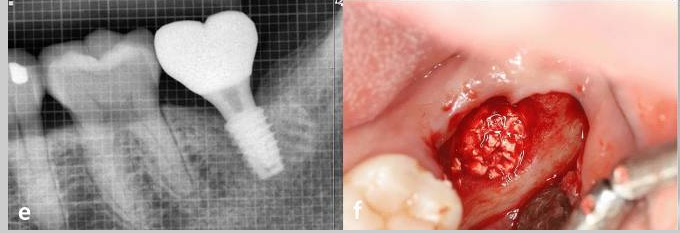

Case photos provided by: Customized three-dimensional printed ceramic bone grafts for osseous defects: a prospective randomized study.

Serial clinical and radiographic images of the experimental group receiving customized 3D-printed ceramic bone grafts. (a ) preoperative panoramic radiograph of tooth #37; (b ) postoperative panoramic radiograph after surgical extraction of tooth #37 with GBR using OSTEON 3D and Collagen Membrane; white asterisk indicates grafted bone material; (c ) CBCT image before the implant placement at visit 5; (d ) panoramic radiograph after implant fixture installation; (e ) panoramic radiograph after final implant final prosthesis; (f ) clinical photo of bone grafting; (g ) 3D digital image of design for fabrication of customized 3D printed ceramic bone grafts (OSTEON 3D).